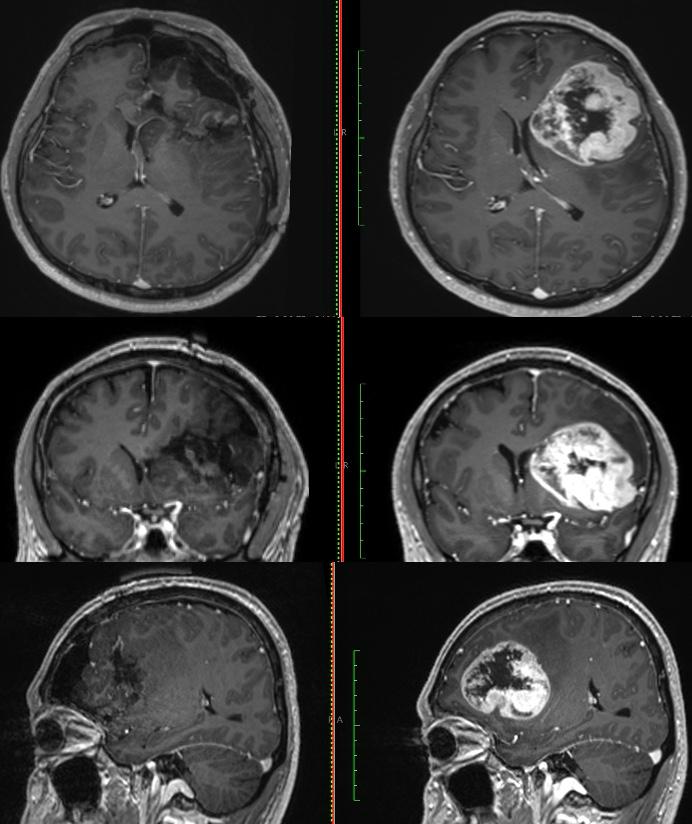

● Gracias al profesionalismo del equipo del servicio de neurocirugía del ISSSTE, un derechohabiente de 54 años recuperó habilidades de lenguaje y motricidad que perdió en dos meses debido a un tumor cerebral.

Una semana después del procedimiento de alta complejidad, el derechohabiente fue dado de alta para completar su recuperación en casa luego de que especialistas en neurología y de diversas áreas retiraron exitosamente un tumor cerebral a un derechohabiente de 54 años, quien permaneció despierto durante el procedimiento que duró siete horas en el Centro Médico (CMN) “20 de Noviembre”, perteneciente al Instituto de Seguridad y Servicios Sociales de los Trabajadores del Estado (ISSSTE).

El neurocirujano a cargo de la operación, Cuauhtémoc Gil Ortiz Mejía, informó que, en coordinación con la especialista en Neuropsicología, se decidió practicarle al derechohabiente un procedimiento llamado craneotomía con paciente despierto, a fin de regresarle las habilidades de lenguaje y motricidad que perdió paulatinamente en un lapso de dos meses por la presencia del tumor.

“El procedimiento realizado en agosto fue de alta complejidad, tuvo una duración de siete horas y se utilizó tecnología de vanguardia, como un neuronavegador cerebral,un microscopio quirúrgico, aspirador ultrasónico, craneotomo eléctrico, neuroestimulador eléctrico de la corteza cerebral, neuromonitoreo transoperatorio y equipo médico de neuroanestesia”, detalló.

Para determinar la realización de este procedimiento y conocer el orígen de los síntomas, explicó, el equipo médico del Instituto le realizó al derechohabiente estudios de tomografía y resonancia magnética.

“Se realizó tomografía de cráneo y, ante los hallazgos, se le practicó una resonancia magnética; posteriormente, se le detectó un tumor de características malignas en la región frontal premotora izquierda”, detalló.

El neurocirujano y miembro del Comité de Cirugía de Epilepsia y de Neurooncología, informó que el paciente recuperó inmediatamente sus funciones luego de la cirugía, por lo que fue dado de alta una semana después de haber sido intervenido para completar su convalecencia en casa, antes de continuar con el tratamiento complementario.

Este procedimiento se suma al realizado en julio de este año, en el que la paciente Yolitzin Salgado, de 34 años, también recuperó su salud y calidad de vida, gracias al profesionalismo del personal médico del Instituto.

Durante la intervención participaron el neuroanestesiólogo, Jesús García Cuevas; la Neuro psicóloga, Erika Graciela Meza Dávalos; así como los residentes de neurocirugía Francisco Castañeda Aguayo, Carlos Alberto Razo Vite, Salvador Guillermo Cabrera Medina; el psicólogo Diego Islas Almazán; los residentes de Anestesia, Daniela Santamaría Solís, Oscar Chimal García; la enfermera instrumentista, Carolina Reyes Iturbide; y la enfermera circulante, Gabriela López Montelongo.